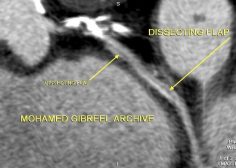

Long dissecting flap

A long dissecting flap for 32mm length dividing the LCX into two lumens a larger one with average diameters of 2 mm and a smaller one with average diameters of 1.5 mm in cross section. The smaller lumen shows partial thrombosis/non-calcified atherosclerotic plaque causing moderate stenosis.

The dissecting flap ends 14 mm before the apparently patent distal LCX stent.